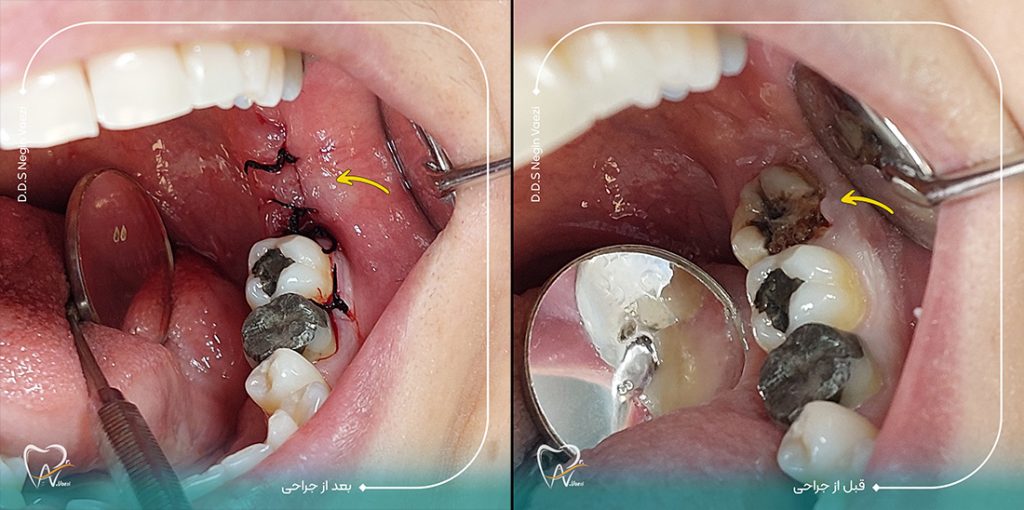

نمونه کارهای جراحی دندان عقل بسیار زیاد هست و تنها تعدادی محدودی از این نمونه کارهای جراحی دندان عقل رو در سایت قرار داده ایم. شما می توانید برای مشاهده نمونه کارهای بیشتر حتما پیج اینستاگرام دکتر نگین واعظی رو دنبال کنید. خب در این نمونه کار که تصویر اون رو در زیر می بینید جراحی دندان عقل توسط دکتر نگین واعظی صورت گرفته است.

در این نمونه کار، دندان عقل بیمار بهصورت کامل رویش یافته بود اما دچار پوسیدگی شدید شده و برای بیمار ایجاد درد و ناراحتی کرده بود. با بررسی گرافی، مشخص شد که امکان ترمیم وجود ندارد و باید دندان بهطور کامل خارج شود.

🔹 این جراحی توسط دکتر نگین واعظی با بیحسی موضعی و در مدت زمان کوتاهی انجام گرفت.

🔹 پس از جراحی، بیمار با رعایت مراقبتهای توصیهشده، دوران نقاهت بدون مشکل را پشت سر گذاشت.

تصویر قبل و بعد از جراحی